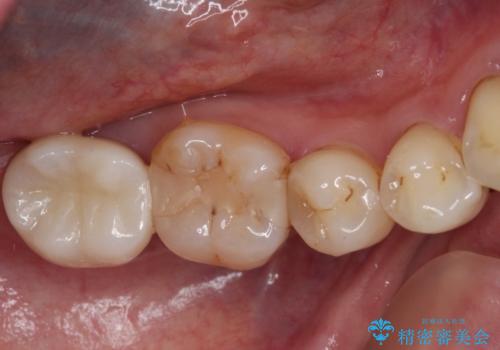

まずは根管治療を行い、その後アンカースクリューを用いて歯を適切な位置まで後方移動させた上で、セラミッククラウンによる補綴治療を行うこととしました。

前方に傾斜したまま補綴治療を行うと、歯間にものが挟まりやすい上に、歯間ブラシなどの清掃器具も通しにくくなるため、清掃性が著しく低下します。

多少治療期間はかかりますが、部分矯正による歯の移動は非常に有意義な治療手段です。